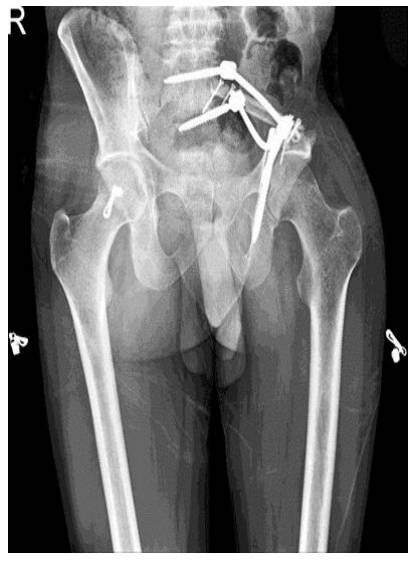

Hastaya 3 kür kemoterapi sonrası geniş rezeksiyon (Tıp I+IV) sonrası fibula ve rod/vida ile rekonstrüksiyon uygulandı

Ameliyat Sonrası: İnternal hemipelvektomi sonrası fibula ve rod/vida ile rekonstrüksiyon görülmekte